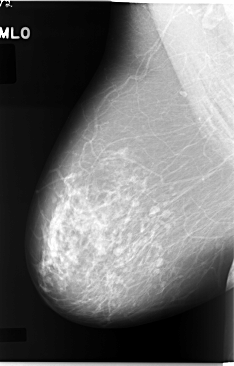

C_0044_1.RIGHT_MLO